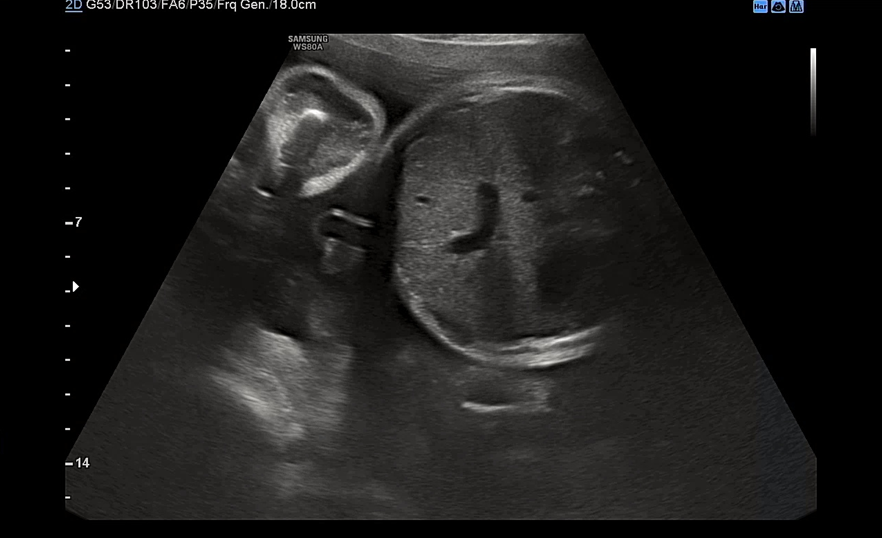

심장도 여전히 잘 뛰고 있고 bpd 7.67cm, ac 26.65cm 정도 나왔다. 원래 주수에 비해 머리가 작은 편이고 배는 딱 적당한 편이었는데 이번주에는 복부가 빵빵해졌다.

다리는 5.96cm 정도로 평균보다 긴 편이라고 하셨다.

이 날 우리 아기는 배에 얼굴을 파묻고선 얼굴을 보여주지 않았다. 아니 지난주에는 그렇게 잘 보여주더니 이번엔 얼굴을 돌릴 기미가 1도 안보였다. 요건 얼굴을 돌린 상태에서 귀만 살짝 보여준 모습.

눈이 살짝살짝 보이다가도 푹 다시 파묻어버리는. 다음 검사때에는 초코우유를 먹여야겠다며 남편이 어찌나 아쉬워하던지 모르겠다. 초음파 검사를 마치면 항상 원장님께서 궁금한 거 없냐고 여쭤보시는데 다른 임산부들은 뭘 물어볼까? 이제 운동을 조금 늘려도 되냐고 여쭤봤는데 무리되지 않는 선에선 괜찮다고 하셨다. 아주 막달이 아니고선 운동은 크게 권장되지 않는 느낌이다. 아기도 너무 잘 자라고 있고 내 컨디션도 너무 좋아 별로 물어볼 게 없었다. 사실 이 날 백일해 주사를 접종하기로 했는데 백신이 떨어져서 접종을 하지 못했다. 34주 전까지는 접종이 권장되는데 원장님께서 소아과나 정형외과에 물량이 있을 수 있으니 가까운 곳으로 전화를 해보라고 하셨다. 일단 2주 뒤 진료라서 그때 병원을 와보고 백일해 주사가 또 없으면 가까운 병원에 전화를 돌려보기로 했다. 이제 30주가 되니 출산용품 리스트에서 남은 물건들도 모조리 다 구입하고 빨래도 시작해야 한다. 엄청 일찍부터 이것저것 알아보고 준비한 거 같은데 한도 끝도 없는 출산 준비. 시간이 점점 부족한 기분이다.